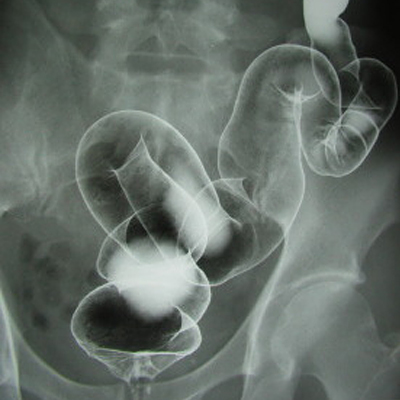

注腸X線検査

肛門から柔らかい管を入れ、大腸にバリウム液を注入した後に空気を入れてX線にて大腸を調べるタイプの検査です。検査の前日は、消化器内の食べ残りが少くなるように検査食をとり、下剤で大腸をきれいにします。